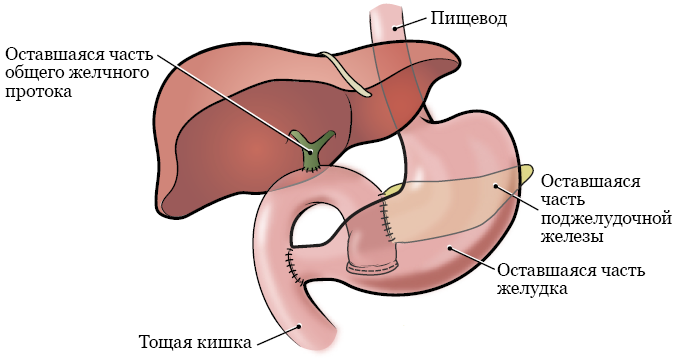

Фотографии медицинских исследований инсулиномы и синдрома Триады Уиппла